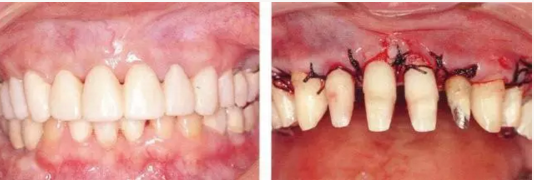

▲圖16-1~3

▲圖16-1~4 56歲,女性?;加腥谘乐苎浊蚁骂M磨牙區(qū)缺失,可以看到上頜前牙區(qū)有前突的現(xiàn)象。左上1和右上1無法保留。